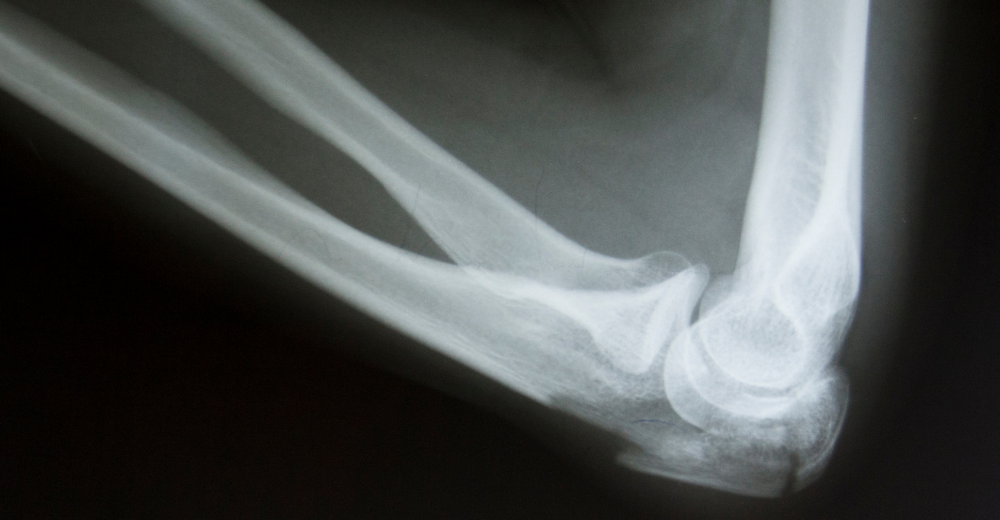

L’RX Gomito, conosciuto anche come radiografia del gomito, è un esame radiologico che utilizza i raggi X per ottenere immagini dettagliate delle ossa del gomito. Questa procedura permette ai medici di individuare lesioni, fratture e altre anomalie, fornendo una visione completa dell’articolazione. Al Poliambulatorio S-Medical Group di Sora, ci avvaliamo di tecnologie avanzate e specialisti esperti per offrire un servizio diagnostico di altissima precisione.

Grazie a un RX Gomito è possibile visualizzare chiaramente le strutture ossee che compongono l’articolazione, tra cui ulna, radio e omero. Questo esame permette di identificare con precisione:

• Fratture e microfratture

• Lussazioni o dislocazioni

• Segni di artrite o artrosi

• Calcificazioni e depositi minerali anomali

• Alterazioni ossee dovute a condizioni degenerative